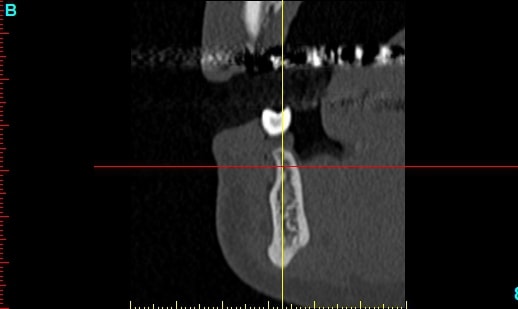

lésion apicale sur 42 risque de contamination sur la vis en regard..

N'ayant aucune donnée j'essaie d'abord de faire le tri,avant de mettre les mains dedans...je raisonne comme en implanto, quand il y a un foyer infectieux à distance proche (42) je pense qu'il y a un risque...

Pour la lésion de 42, ca peut être lié à la genio. Forage hasardeux? Mais je vote plus pour une lésion endo/paro

Celui qui a fait l'attelle, après l'ortho, lui aait dit ça permettra d'attendre après vous ferez des implants, donc je croyais que c'était une solution envisageable...avant d'avoir vu le scan.

je passerais les clichés, pour avis.

pas simple me semble t il, mais un gros avantage... la sensibilité fait partie du passé, donc je peux "planter" profond....